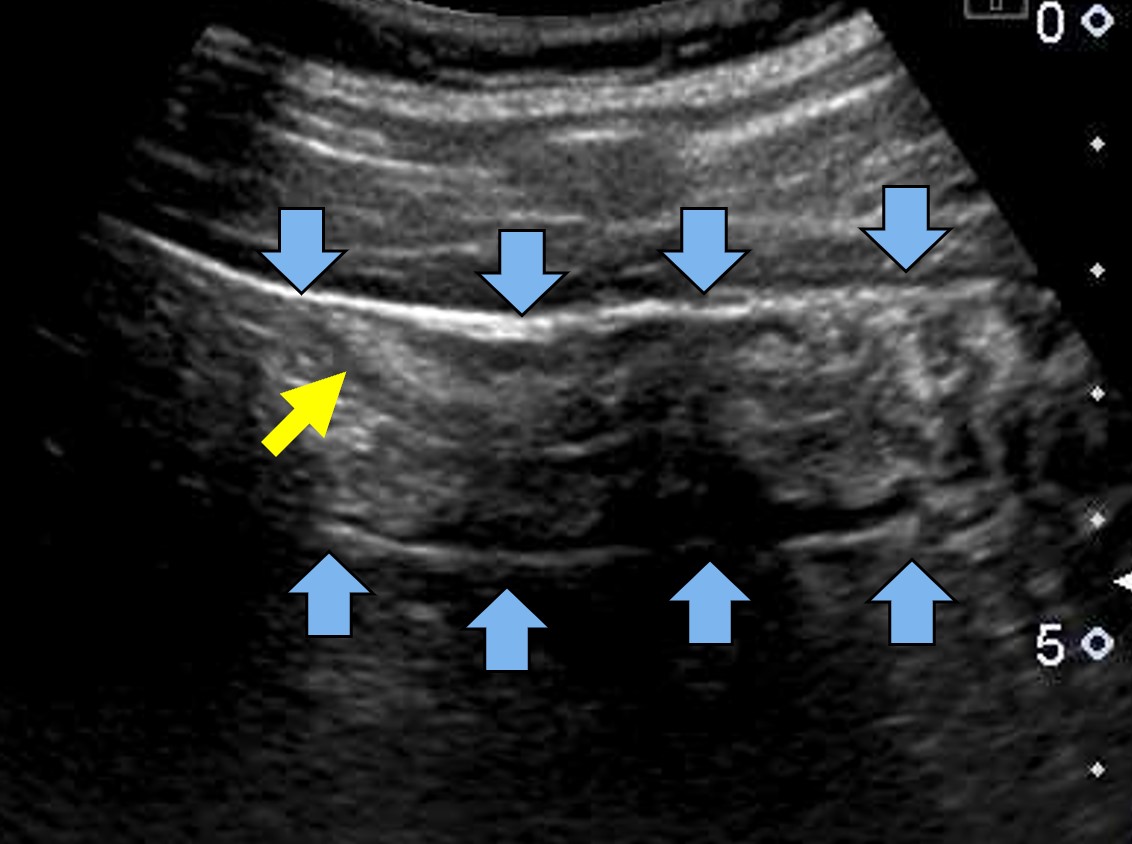

- 腹部 CT スキャン:このスキャンは、結腸が空であるか、リンパ節の肥大がない場合に、細菌性大腸炎を診断するために使用できます。

- 骨盤 CT スキャン:このスキャンにより、結腸壁が肥厚しているかどうかがわかる場合があります。